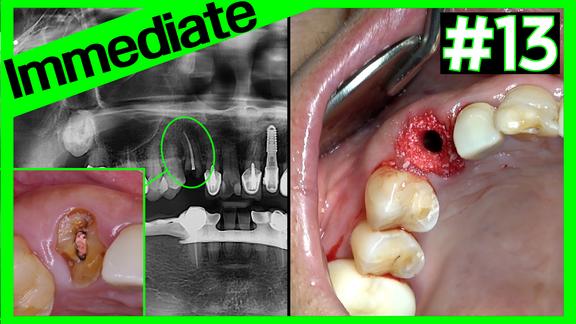

#16 Implant Removal & Immediate Placement

Online Surgery

Views 27